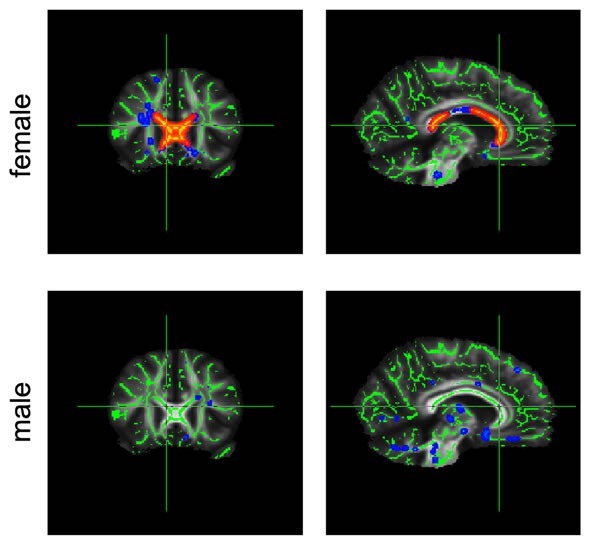

corpus callosumChanges in diffusion in the corpus callosum (marked red) are much greater in obese female participants than in their male counterparts.

Axons are responsible for transmitting signals in the brain, and myelin is an insulating layer around the axons. With increasing body mass index (BMI), the mobility of the water changed, both along the nerve fibers and also across them. In both genders, the researchers found slower diffusion along the nerve fibers. In female participants only, they also found increased movement across the fibers. Both findings could indicate – possibly different – degeneration processes.

The differences in diffusion, which are likewise observed in premature aging of the brain tissue, were more dominant in female participants and covered a greater area of the corpus callosum. This is the first study to show systematic sex-related differences in the relationship between weight and the brain. This could possibly be because connections between the brain hemispheres generally show differences between men and women.